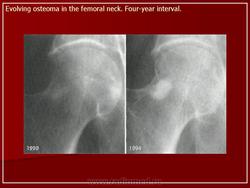

Остеома костей таза зачастую может протекать бессимптомно. Самостоятельные боли, как правило, отсутствуют. Остеомы растут очень медленно, иногда рост их спонтанно прекращается, но после периода затишья они вновь начинают увеличиваться в размерах.

Рентгенодиагностика остеом, как правило, не представляет трудностей. Рисунок опухоли является продолжением рисунка самой кости. Деструктивные изменения и нарушение коркового слоя всегда отсутствуют.

Остеома